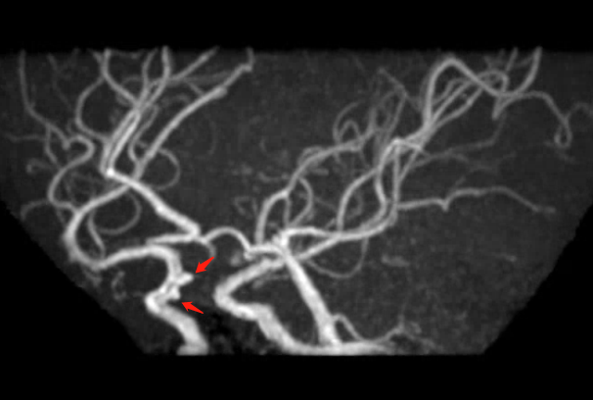

🔆  行头MRI+MRA示:右侧丘脑亚急性脑梗塞;轻度脑萎缩;部分空泡蝶鞍;脑动脉硬化并多组脑动脉轻度狭窄;右侧颈内动脉虹吸段外动脉瘤待排。

术前影像

MRI+MRA

脑血管造影提示右侧颈内动脉颅内段多发动脉瘤(反主动脉弓)

脑血管造影提示右侧颈内动脉颅内段多发动脉瘤